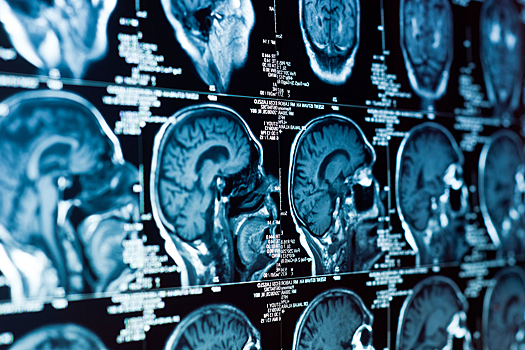

Ученые объяснили: человеческий мозг отличается от мозга других животных масштабной корой, сложной организацией и большим разнообразием клеток. Эти особенности закладываются еще в период развития, в вентрикулярной зоне — области, где стволовые клетки дают начало нервным и вспомогательным клеткам. Чтобы делиться и мигрировать в нужные слои, клетки постоянно перестраивают цитоскелет — внутренний «каркас», определяющий их форму и направление роста.

Работа проводилась на органоидах — моделях человеческого мозга, выращенных из стволовых клеток. Они позволили увидеть, как нарушение работы ARHGAP11A изменяет архитектуру развивающейся ткани. Кратковременное подавление чрезмерно активных сигнальных путей частично устраняло эти дефекты, что говорит о потенциальной управляемости процесса.